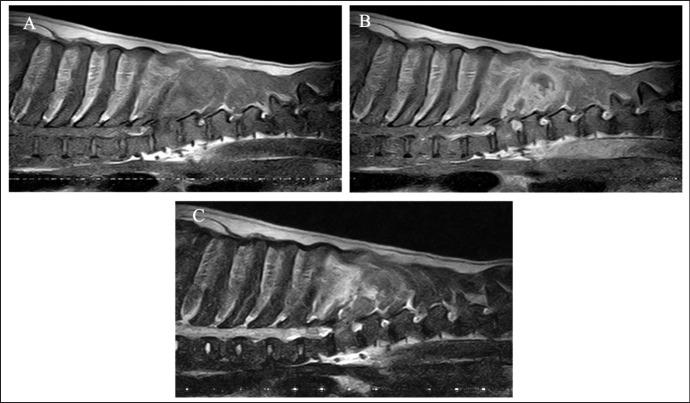

A 9-year-old male Labrador Retriever was presented with a progressing non-ambulatory tetraparesis. CT imaging revealed lysis of the spinous process of T7 and a ring-shaped lesion surrounding the soft tissue of lung fields. T2-weighted MRI showed the spinous processes of T6 to T8 as hyperintense, and the lesion infiltrated into the T7 vertebra and the spinal cord. After euthanasia, the final diagnosis upon necropsy was HS, which was observed in the lung, spinous process, thoracic cord, and the pulmonary hilar lymph node. Moreover, necrotic spots were spread widely through the thoracic spinal cord.

CONCLUSION

一只 9 岁雄性拉布拉多猎犬出现进行性非四肢瘫痪。CT 成像显示 T7 棘突溶解和肺野软组织周围的环形病变。T2 加权 MRI 显示 T6 至 T8 的棘突呈高信号,病变浸润 T7 椎骨和脊髓。安乐死后,尸检的最终诊断为 HS,在肺、棘突、胸髓和肺门淋巴结中观察到。此外,坏死灶广泛分布于胸段脊髓。

结论

本报告概述了一例犬肺、棘突、胸髓和肺门淋巴结的 HS。血管周围肿瘤细胞的压迫导致了缺血性缺陷和胸段脊髓坏死,这迅速导致了进行性四肢瘫痪。尽管诊断困难,但 MRI 和 CT 图像有助于确定预后。据我们所知,这是首例与脊髓坏死相关的犬直接脊髓受累的 HS 病例报告。